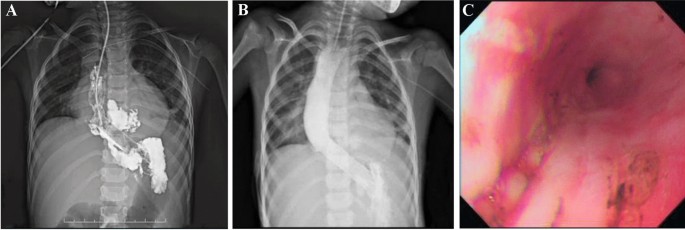

The esophagus of all 14 pediatric patients were imaged using contrast upper gastrointestinal tract radiography, of whom 10 with chemically corrosive esophageal stricture showed that the contrast medium passed through the esophagus slowly and unveiled one or more segments of stenosis along the course of the esophagus, with dilated portions at the upper part of the esophagus, 2 cases of achalasia of cardia featured the stenosis of the lower esophagus as unique beak-like changes with the difficulty in passing the contrast medium (Fig. 4A), 1 case of esophageal perforation caused by balloon dilatation of esophageal stricture (Fig. 5A) showed that the contrast medium had infiltrated the mediastinum (Fig. 5B), and 1 case had esophageal perforation after peroral endoscopic myotomy (POEM) (Fig. 6A).

Two patients with achalasia of cardia (cases 11 and 12) showed remarkable improvement in the symptoms of vomiting (Fig. 4B,C) without the need for further stent placement. Two patients (cases 2 and 11) presented symptoms of vomiting and chest pain 2–3 days after stenting, which were relieved by conservative management without stent removal. Three patients (cases 5, 9 and 10) developed restenosis 3 months after stent removal, but the degree of stenosis had been significantly mitigated compared to before stenting and the lumens at the narrowing were significantly enlarged, with improvement in swallowing difficulty after the new stents were placed (Fig. 7B).

More specifically, 2 patients (cases 5 and 9) failed to meet the follow-up schedules due to parental reasons, but were subsequently readmitted for chest pain and discomfort symptoms that occurred again about 3 months after stent placement. To treat these patients, their stents were removed after the finding of inflammatory granulation tissue hyperplasia at the lower end of the stent in case 5 (Fig. 7A) and stent embedding in case 9 (Fig. 7C). Fortunately, the embedded stent was removed successfully with the help of biopsy forceps (Fig. 7D), but both cases still needed additional stent and balloon dilatation treatment before their symptoms were completely relieved.

The child with esophageal perforation after POEM (case 13) was given an esophageal stent (Fig. 6A), but 7 days after its placement, the patient developed stent migration, which was dealt with by an adjustment of the stent position under endoscopy, consequently leading to the closure of the fistula one and half months later (Fig. 6B,C). The child with esophageal perforation (case 14) underwent closed thoracic drainage for esophageal mediastinal fistula and then received empyema exploration, with esophageal stent placement. However, the patient was found to have stent malapposition 5 days after the operation (Fig. 5B), which required the removal of the original stent and its replacement with an esophageal stent with a larger upper bell mouth (Fig. 5C,D). Two months later, the stent was removed, the fistula healed and the stenosis disappeared.